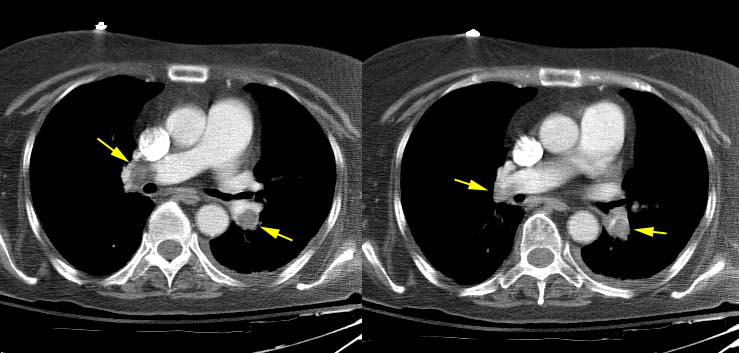

Pulmonary embolsim in a patient with left iliac vein thrombosis

CT PE DVT example

Pulmonary emboli in a lymphoma patient with SVC thrombosis

Massive Pulmonary Embolism